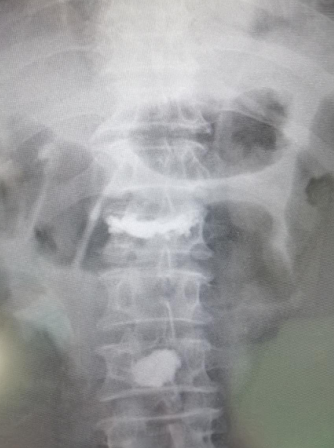

74岁老人骑电动车,被驶过的大货蹭倒,摔成腰1、腰3椎体压缩性骨折,接诊的betway在线登陆采用天玑骨科机器人精准“操刀”,为患者进行了椎体成形手术,24小时后老人已经下地活动,手术获得成功。

患者李大爷,家住丰县,被送到必威官方首页官网betway时,由脊柱科孟磊副主任医师接诊,老人腰1、腰3椎体压缩性骨折,这种压缩性骨折是无法通过普通的卧床静养就能自行恢复的,需要做椎体成形手术,脊柱科尚军主任和手术小组讨论后,决定采用骨科机器人辅助手术。

手术过程中,孟磊副主任医师在骨科机器人的帮助下,精确定位后,在患者后腰部开了一个直径0.5厘米的小孔,手术器械由此进入,先为患者进行腰椎复位,随后,医生在复位腰椎内注入“骨水泥”,完成治疗。